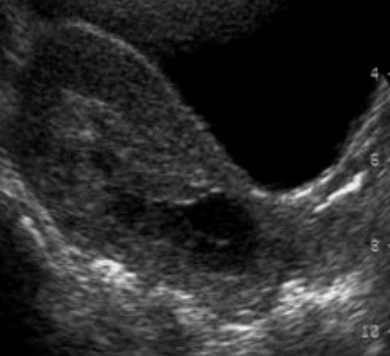

28

Línea endometrial delgada y cuello formado.

¿Qué caracteriza un aborto incompleto?

Restos ovulares retenidos, útero no involucionado, cuello entreabierto o cerrado, hemorragia persistente.

¿Qué hallazgos ecográficos confirman un huevo muerto y retenido?

- Ausencia de vitalidad - Lisis embrionaria - Saco gestacional deformado - Hematomas retrocoriales/placentarios